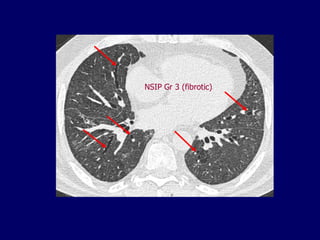

NSIP Gr 3(fibrotic)

NSIP: initial reportsof CT spectrum of findings: • Ground glass opacification with or without areas of consolidation • Linear opacities and reticular pattern, but honeycombing limited or absent • Lower zone predominance, may be subpleural predilection Park et al Radiology 1995;195:645 Hartman et al Radiology 2000;217:701

NSIP A fibrosing lungdisease in which ground glass is predominant and honeycombing is minimal or absent, often with a peripheral basal distribution

The Many ‘HRCTFaces’ of NSIP Honeycombing not a prominent feature !!!!